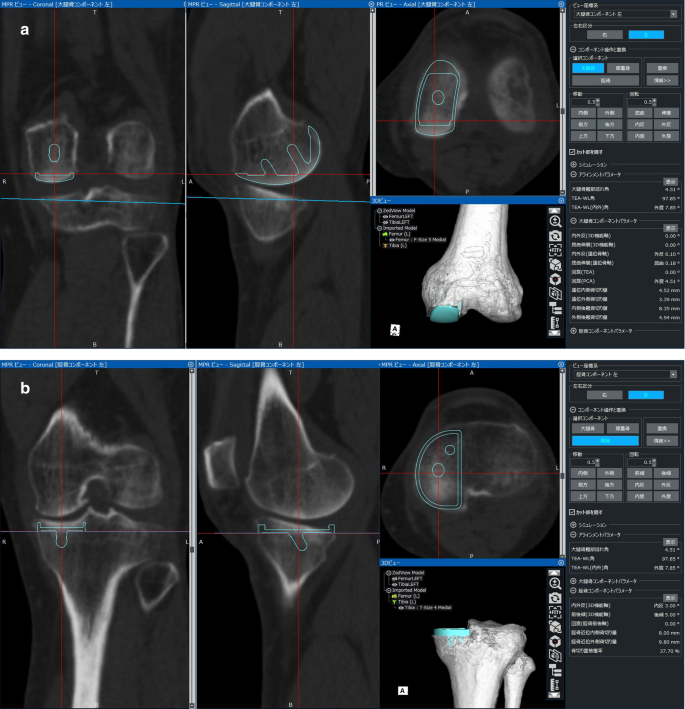

Dependence Of Knee Range Of Motion On The Alignment Of Femoral And Tibial Components After Medial Unicompartmental Knee Arthroplasty Springerlink

link.springer.com